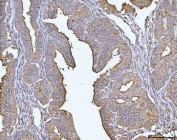

IHC staining of FFPE human bladder epithelial carcinoma tissue with MUC1 antibody. HIER: boil tissue sections in pH8 EDTA for 20 min and allow to cool before testing.